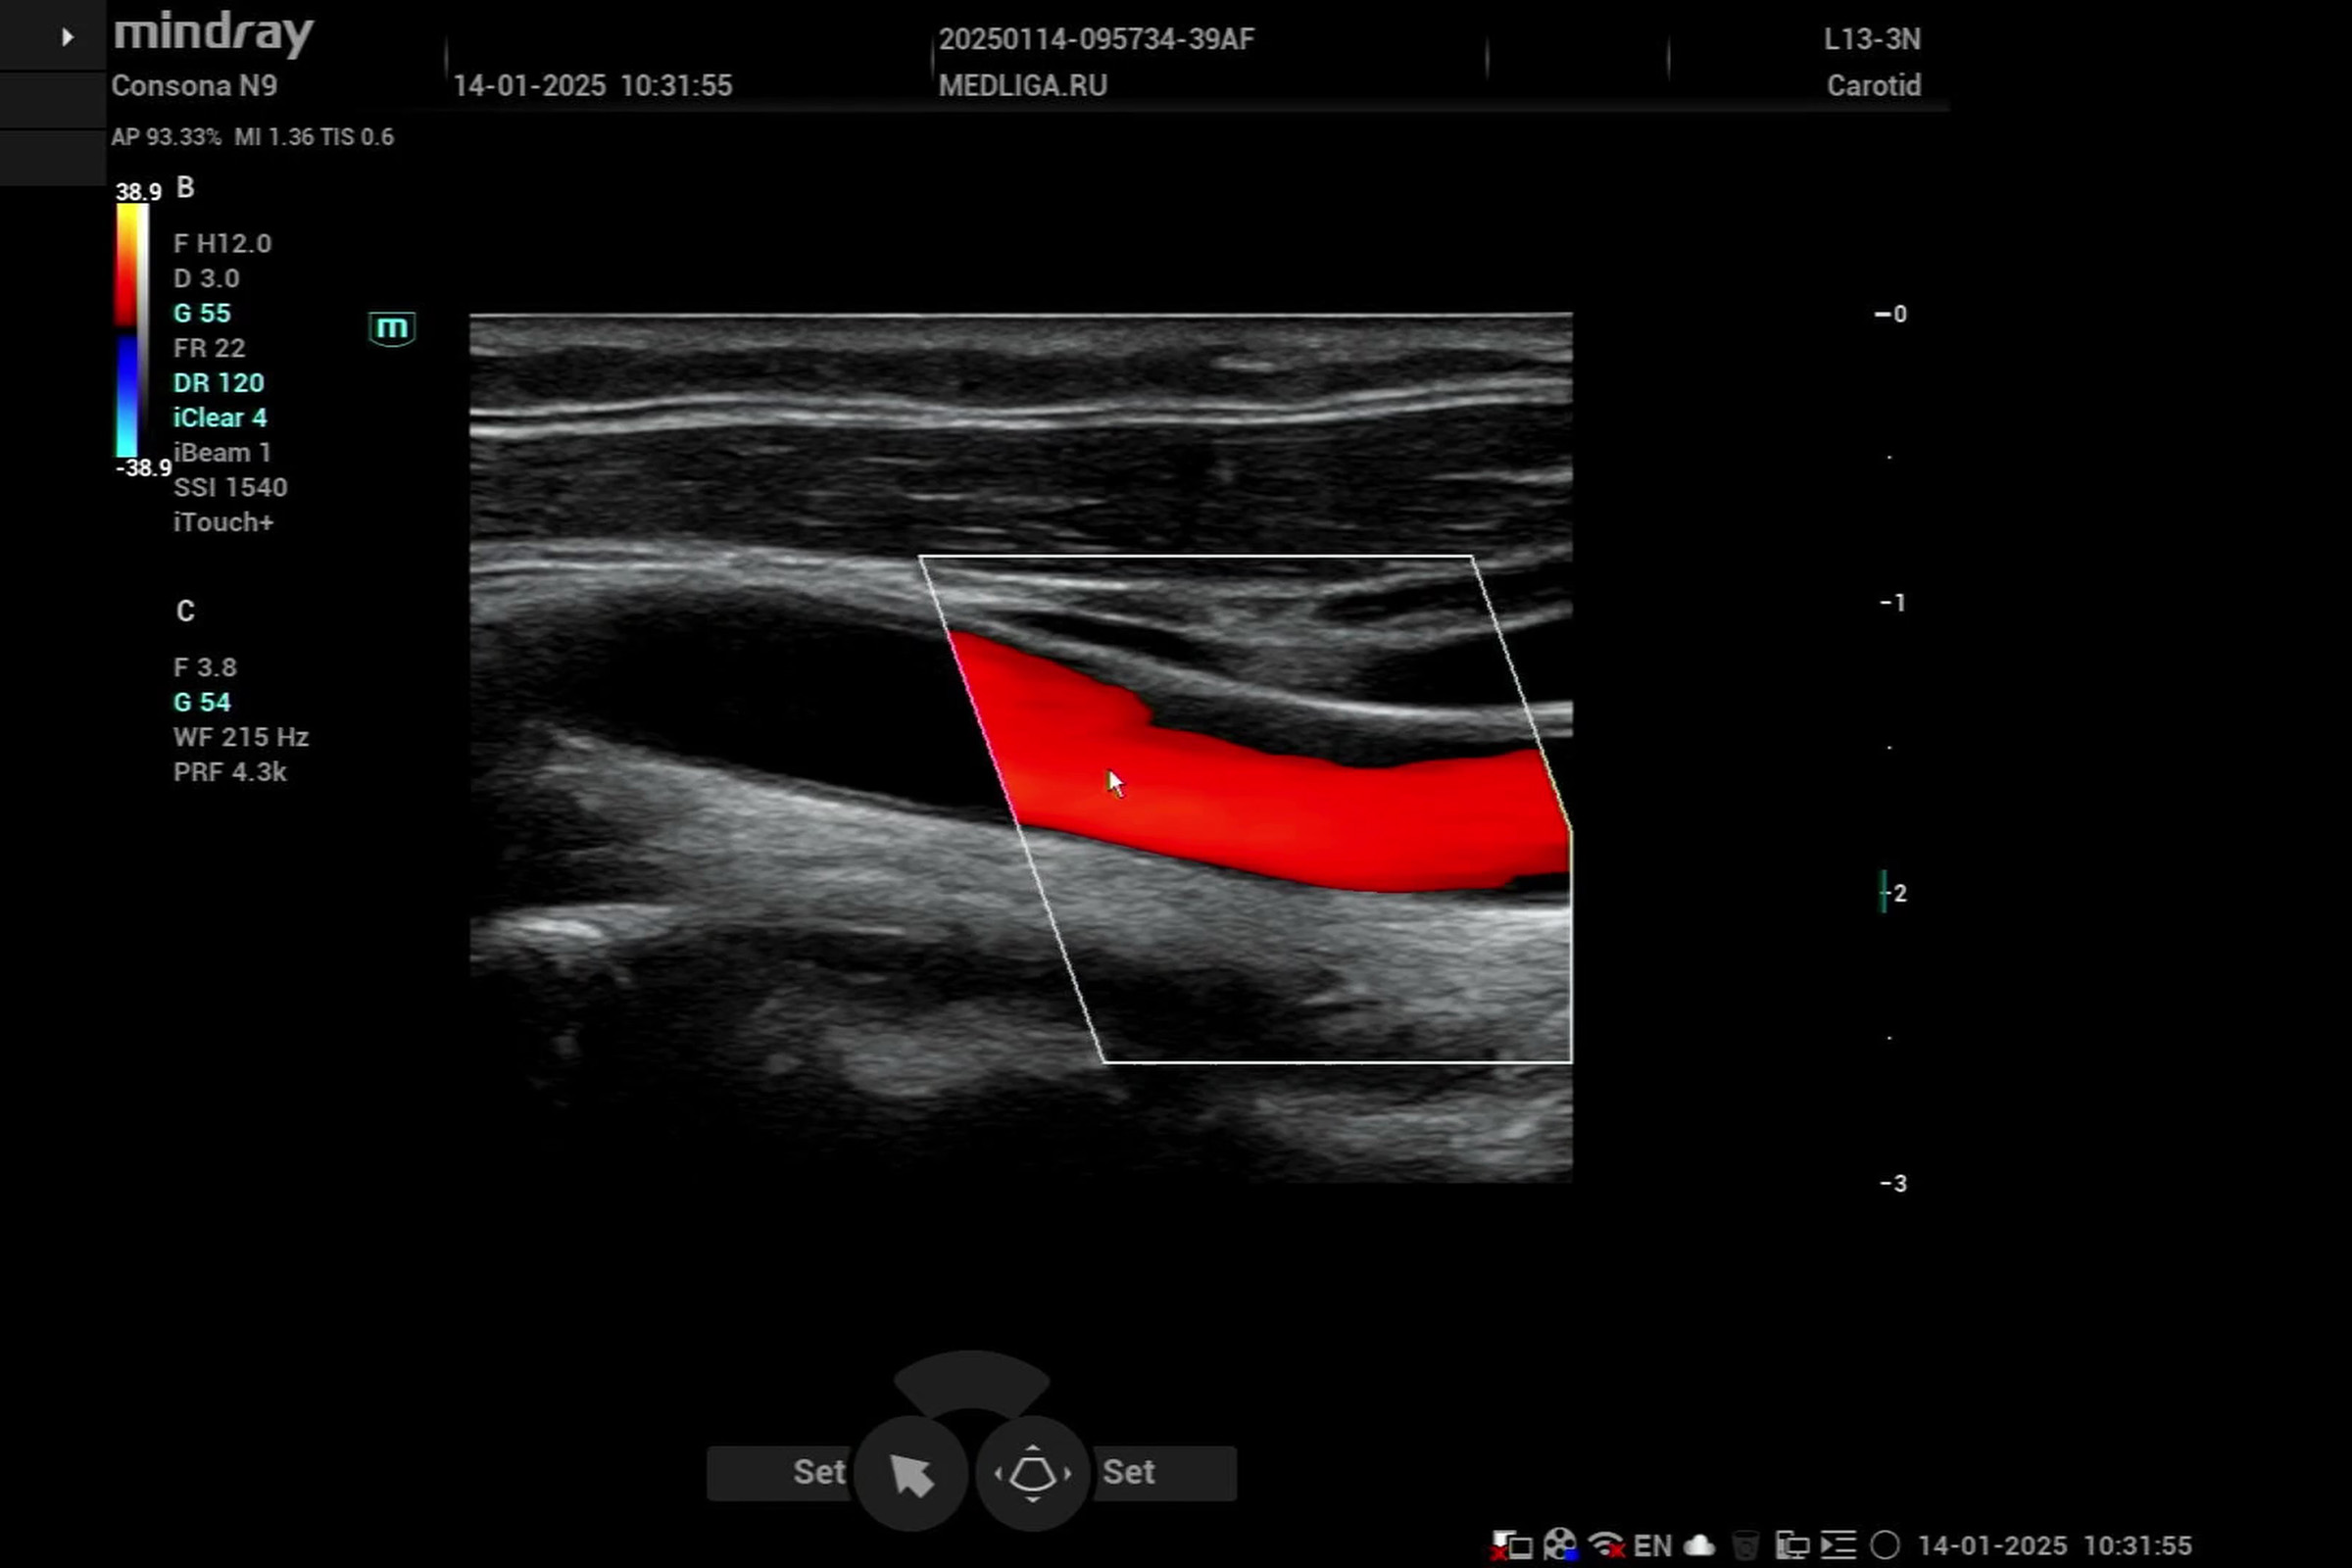

Видео узи артерий

Видео узи артерий 107 фото